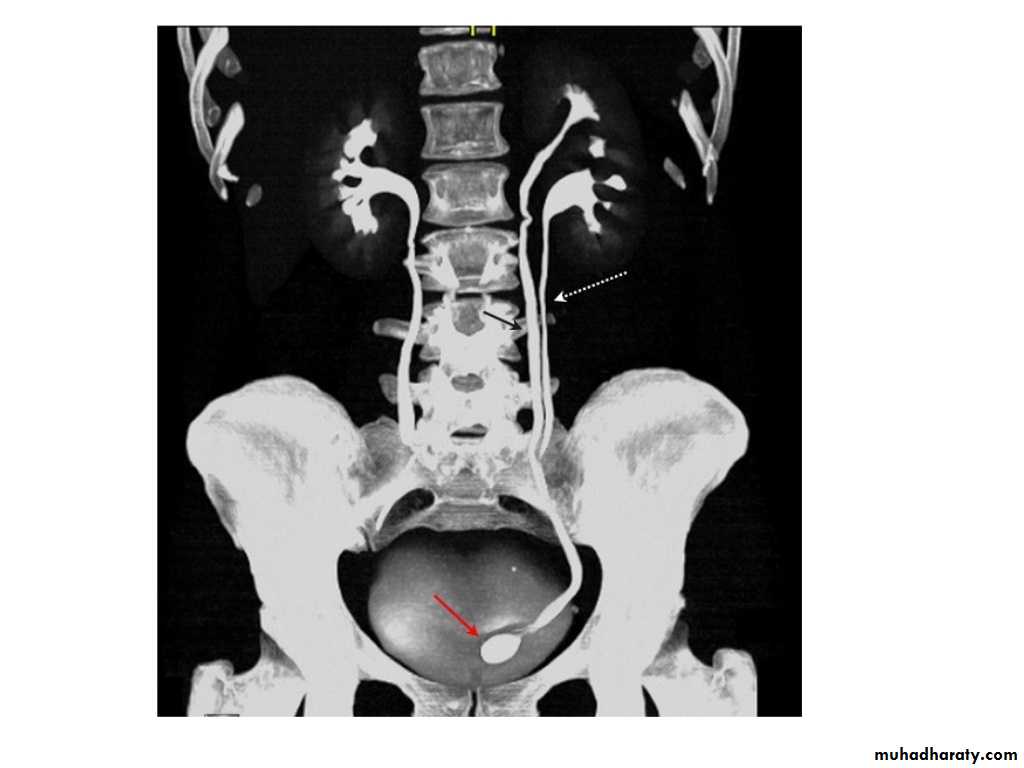

IVU shows

1. The kidneys at low position .2.Close to the spine with long axis parallel to the spine

3. Malrotation manifested by medially directed calyces.

4- The renal pelvis and ureters are anterior and lateral in position.

5- Hydronephrosis and calculi highly associated.